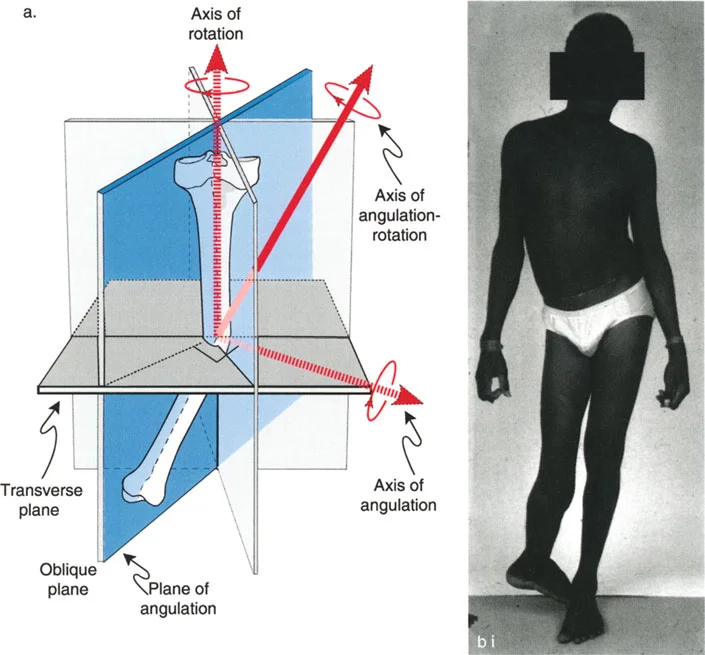

غالباً ما تتواجد هذه التشوهات معاً، مما يجعل الحالة أكثر تعقيداً. فمثلاً، قد يكون عظم الفخذ منحنيًا وفي نفس الوقت ملتفاً. هذا التداخل يخلق "تشوهاً ثلاثي الأبعاد" يتطلب فهماً عميقاً وكفاءة عالية لتصحيحه.

أهمية التصحيح ثلاثي الأبعاد

عندما يكون العظم مشوهاً في كل من الانحراف الزاوي والدوران، فإن أي محاولة لتصحيح أحد الجانبين دون الآخر قد تؤدي إلى نتائج عكسية أو حتى مضاعفات خطيرة. على سبيل المثال:

تحديد مستوى التشوه بدقة

إن تحديد المستوى الدقيق للتشوه الدوراني هو أحد أهم الخطوات في التخطيط الجراحي. على الرغم من أن الدوران هو تشوه زاوي في المستوى المستعرض، إلا أن موقعه على طول العظم (قريب من المفصل أو بعيد عنه) يؤثر بشكل كبير على كيفية تصحيحه وتأثيره على الأنسجة المحيطة.